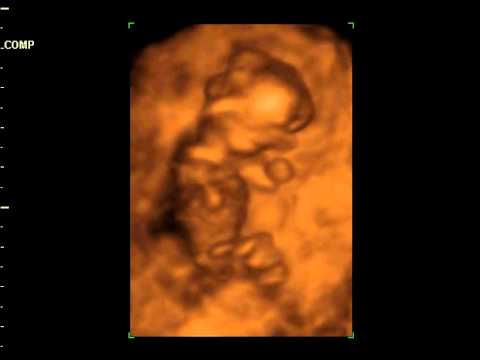

Cordelia 4D Scan, 05/08/2011 - YouTube

Cordelia 4D scan, 05/08/2011 Jonathan Cheetham. Subscribe Subscribed Unsubscribe 6 6. Loading The 3d 4d Ultrasound Experience at Goldenview Ultrasound Chicago, Boston,NYC &San Antonio - Duration: ... View Video